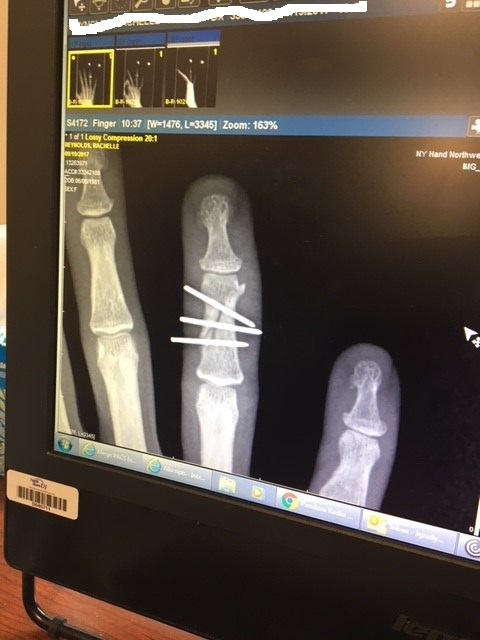

leash wrapped around fingers coming out of the water - wave sent my board flying and fractured my finger badly, needing surgery - lucky I didn't lose it, learned that the ocean is infinitely powerful and not to drag my board out by the leash anymore

finger.jpg

finger 2.jpg